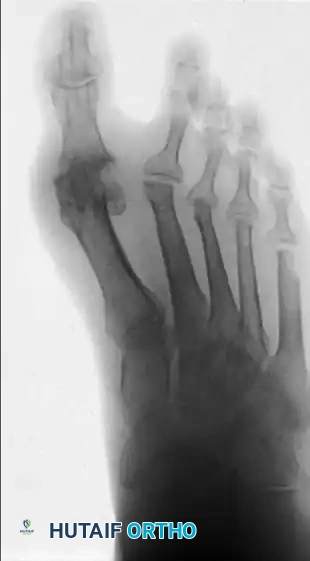

ARTHRODESIS OF THE FIRST METATARSOPHALANGEAL JOINT

This specific alignment allows for a normal toe-off during the terminal stance phase of gait and accommodates a standard shoe heel height. Excellent gait patterns and improved first-second intermetatarsal angles are routinely achieved. Rarely is a proximal first metatarsal osteotomy necessary in conjunction with the arthrodesis.

Arthrodesis vs. Excisional Arthroplasty

Comparisons between first MTP arthrodesis and excisional arthroplasty (e.g., Keller procedure) heavily favor arthrodesis. Arthrodesis provides superior pain relief, better dynamic balance, improved cosmesis, and a greater ability to fit the foot into a normal shoe.

While one older study suggested patient satisfaction was lower after arthrodesis despite better objective foot function, modern prospective, randomized studies (such as Grondal et al.) comparing first MTP arthrodesis to first metatarsal head resection found no significant difference in deformity recurrence, lateral forefoot pressure, or patient satisfaction. However, given the small sample sizes in these studies, the consensus among master surgeons remains that even with a well-preserved hallux MTP joint, fusion is a more definitive and satisfactory procedure than attempts at joint preservation in the rheumatoid patient.